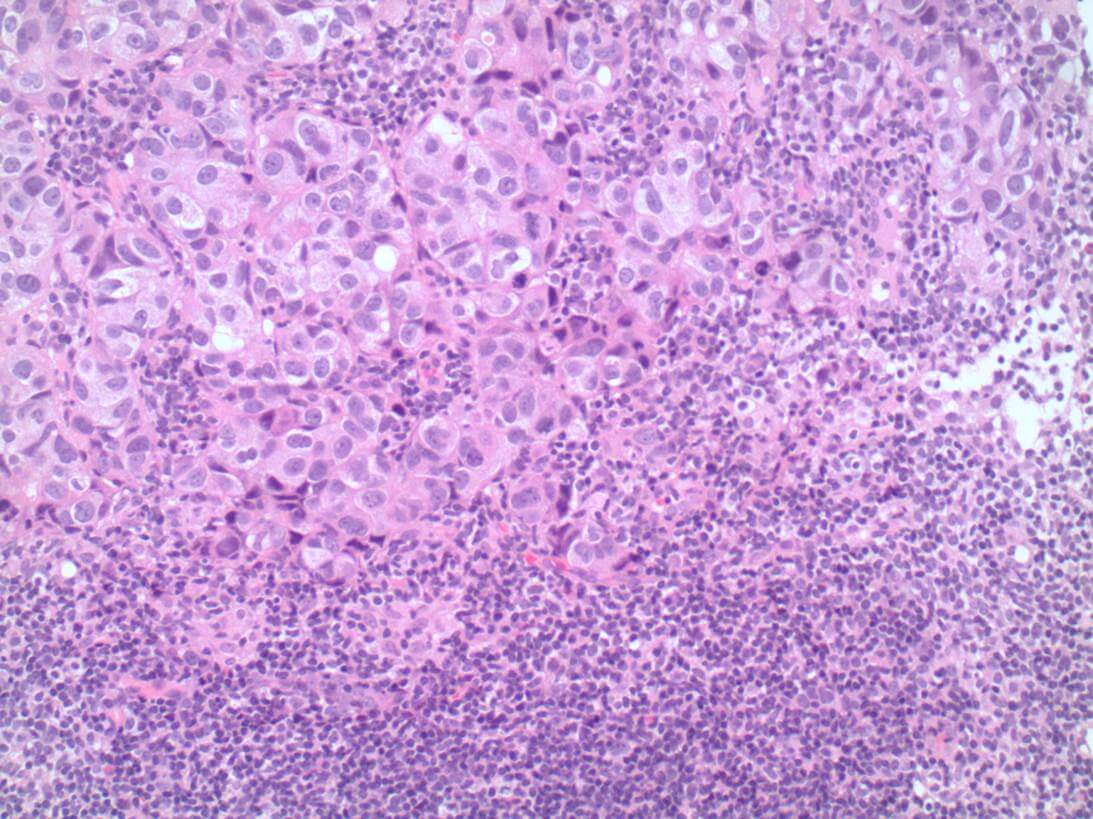

Staging

In early breast cancer, this is primarily based on the size of the invasive carcinoma and the status of the associated axillary lymph nodes. For patients with clinically node negative disease, sentinel lymph node biopsies are often used to assess the nodal status. In some cases, often those patients with higher risk tumours, an intraoperative “frozen section” will be performed proceeding to axillary lymph node dissection in the same procedure if positive (Figure 3 –metastatic carcinoma in a lymph node). In others, the sentinel nodes will be assessed post-operatively with the definitive breast excision specimens. The most recent international staging system (AJCC 8th Edition) also incorporates grade, hormone and HER2 receptor status to assign a prognostic stage, highlighting the significant impact of targeted therapies on outcome.

![This image depicts metastatic carcinoma in a lymph node. Professional medical imaging for clinical reference and educational purposes. [umbracoNodeId=9800]](/assets/image/jpeg/metastatic-carcinoma-in-a-lymph-node-7ngijf4jevkkrsd5d5ejqj.jpg)

Figure 3: Metastatic carcinoma in a lymph node